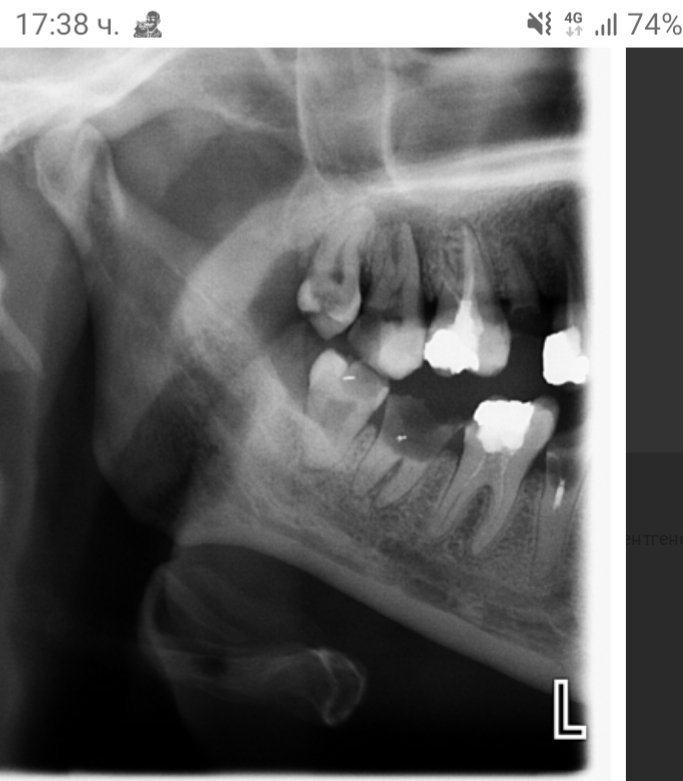

Лечението на хроничен периодонтит на млечни зъби включва премахване на инфекцията и възстановяване на здравето на зъбите. Обикновено се извършва кореново канално лечение, което включва почистване на кореновия канал и запълване със специални материали. При наличие на фистули и гноене може да се наложи и антибиотична терапия. В случай на продължаващи проблеми, консултацията с орален и лицево-челюстен хирург или ортодонт може да бъде от полза.

Ако пълнежът излезе извън коренови канал, това може да създаде проблеми. Излизането на пълнежа може да доведе до инфекция или реинфекция на зъба. В такъв случай е необходимо да се консултирате със зъболекар, който може да прецени дали е необходимо повторно лечение на кореновите канали или други процедури за спасяване на зъба.